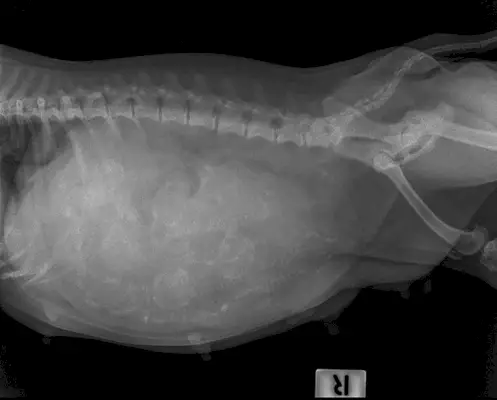

- rentgen

Tento týden je vhodný čas vzít svého pitbulla k veterináři, aby potvrdil březost, protože během ultrazvuku lze vidět srdeční tep plodu a váš veterinář bude schopen jemně nahmatat váčky, když prohmatává břicho vašeho psa.

Veterinářsmětbýt schopen určit možný časový rámec pro dodací lhůtu, protože psí březosti trvají mezi 62 a 64 dny. Nebudou však schopni určit přesné datum, takže byste se měli začít připravovat na štěňata.